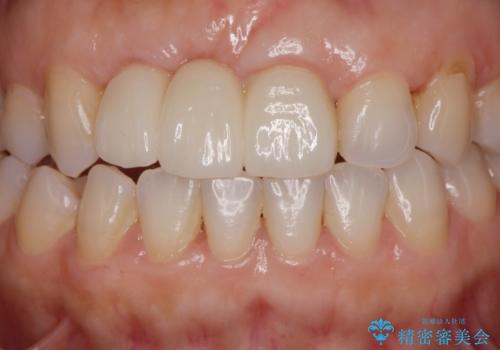

歯周外科をおこなったことで歯ぐきのラインを整え、脱離しないような前歯のブリッジを作製することができました。